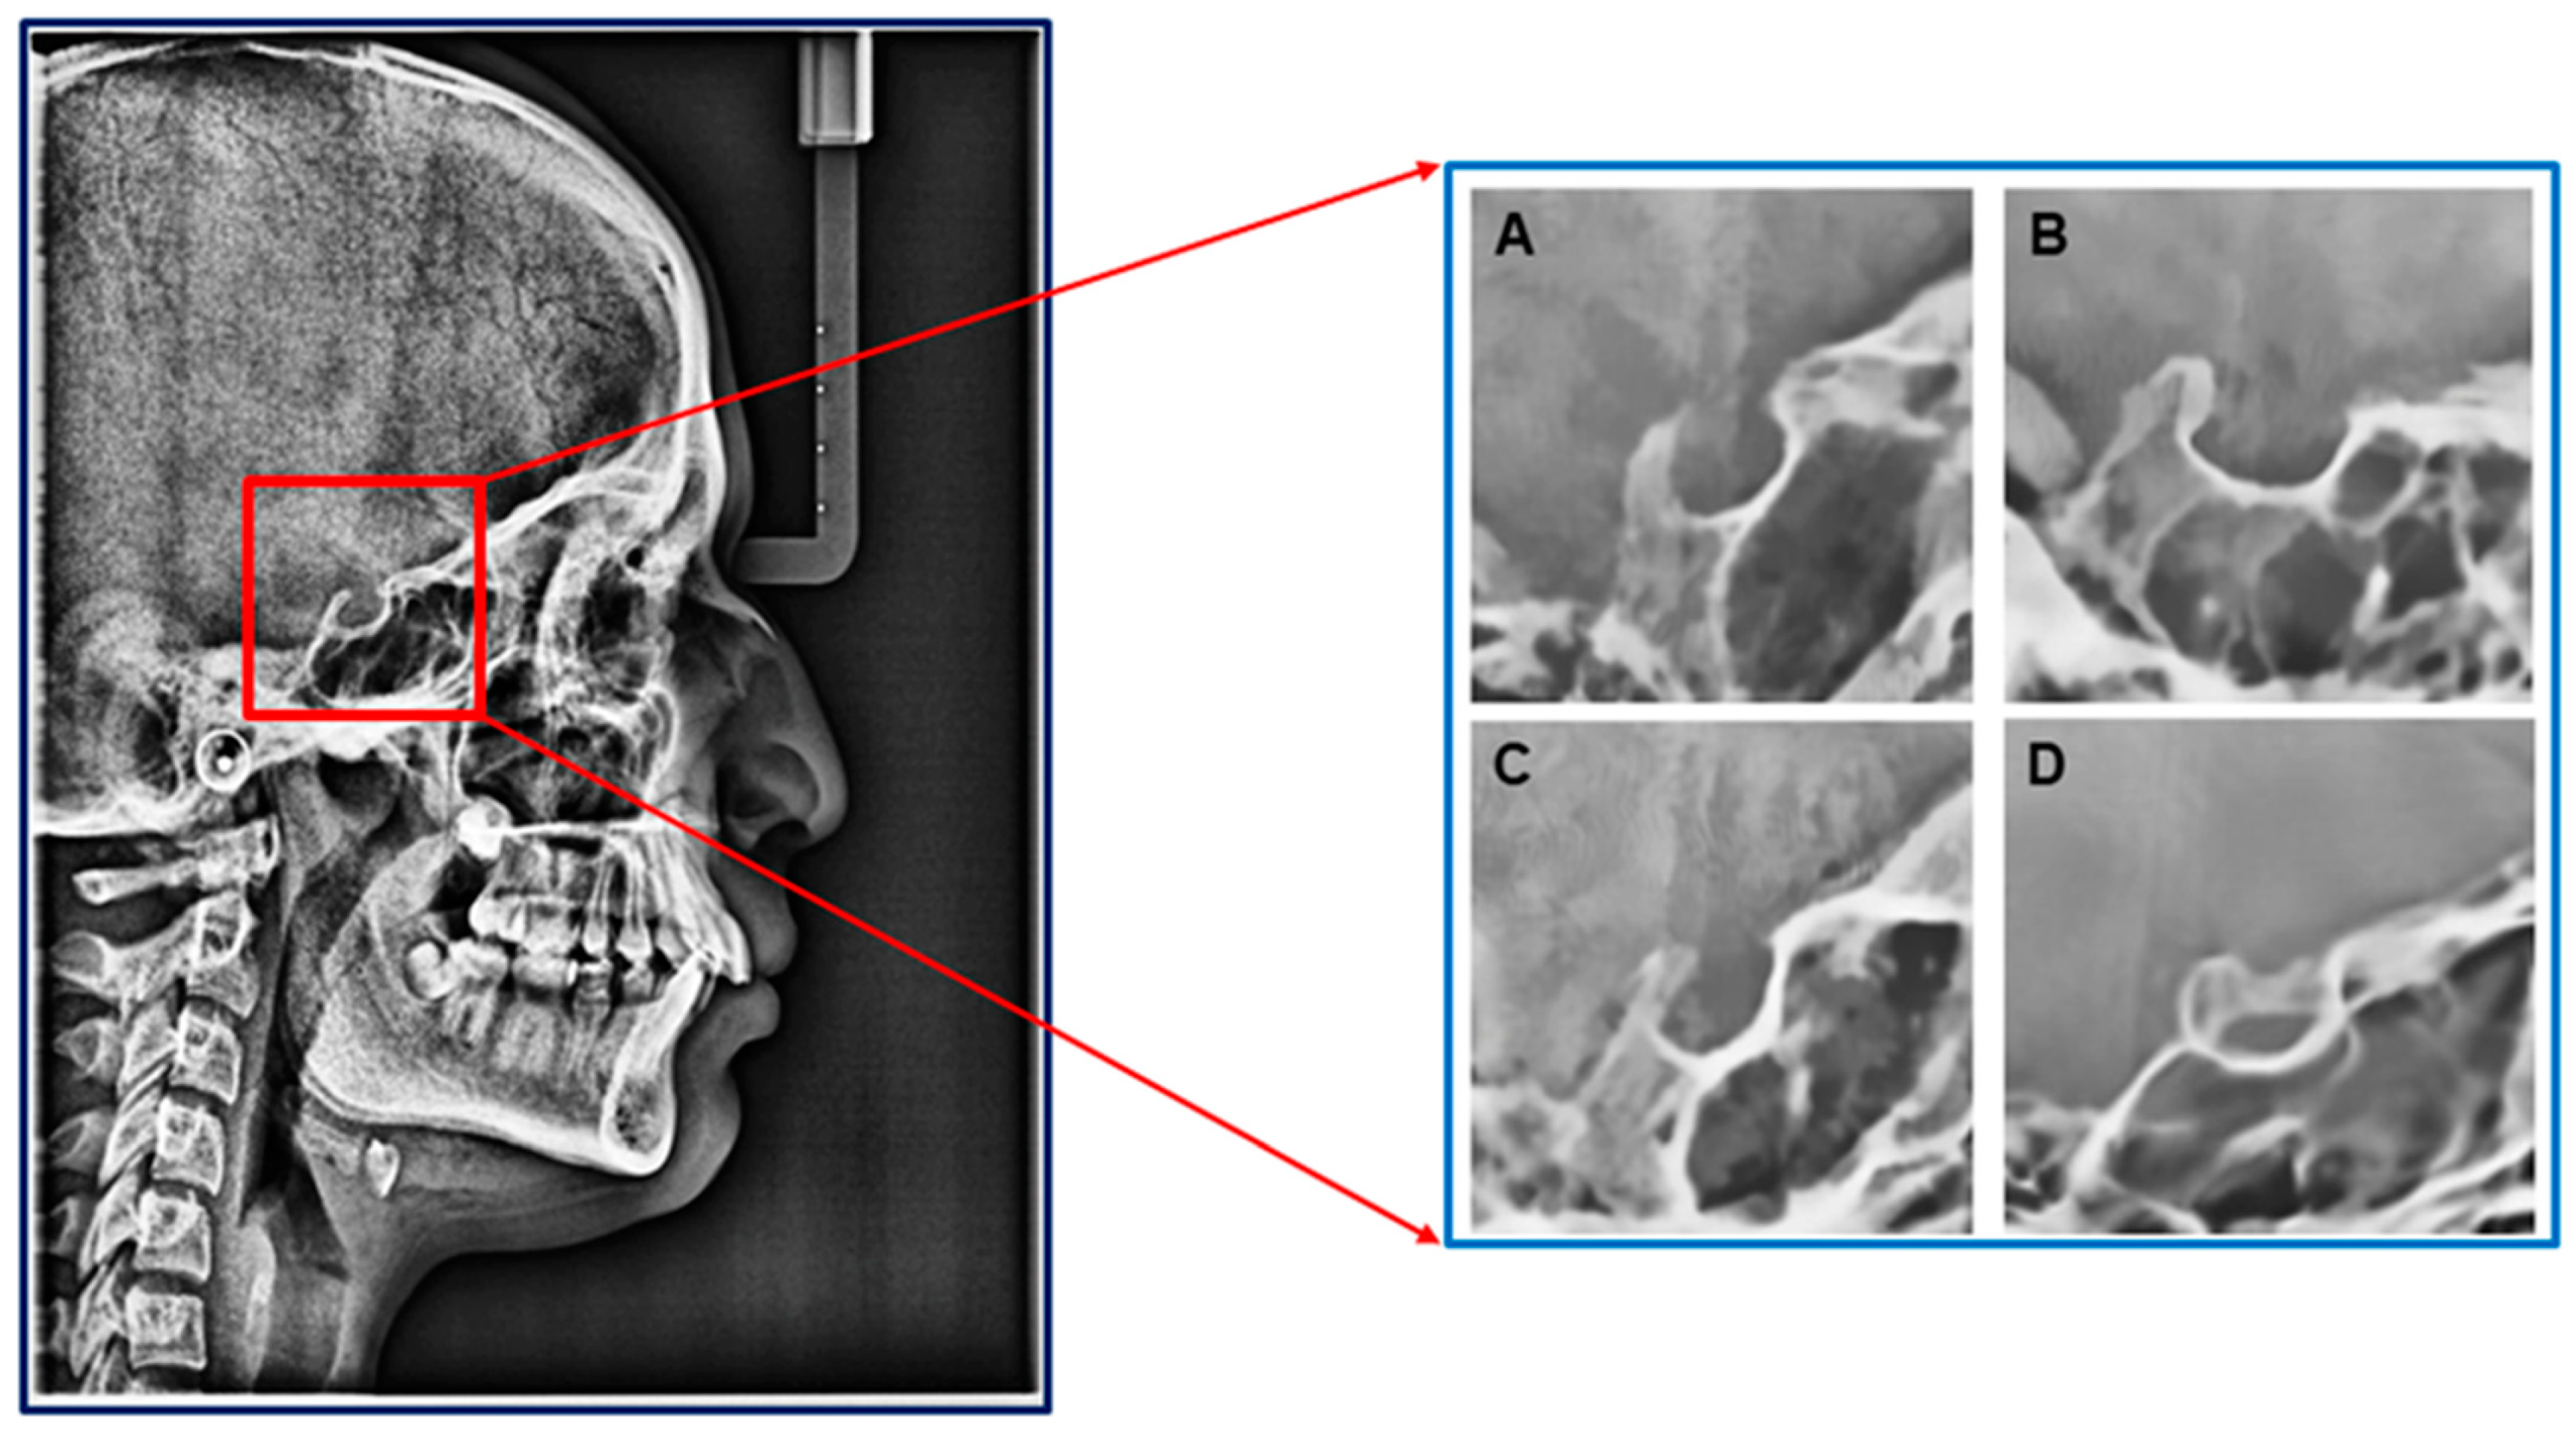

The lateral cephalogram (lat ceph) is an essential tool for orthodontists when planning treatment for craniofacial deformities. Accurate traceability and identification of different cephalometric landmark points on radiographs allow orthodontists to diagnose and evaluate orthodontic treatment. A landmark point (Sella point) marked at the centre of Sella Turcica (represented with ST) is widely used in orthodontics. Sella Turcica is an important structure in understanding craniofacial deformities by analysing its characteristics (shape, size, and volume) [1,2]. The pituitary gland is enclosed within the ST, which is a bony structure with a saddle shape. It has two clinoid projections, anterior and posterior, that extend across the pituitary fossa [3,4]. The size of these projections can vary, and when they converge, it is known as Sella Turcica Bridging (STB). This condition can lead to dental deformities and disrupt pituitary hormone secretion [5,6]. Camp has identified three types of standard Sella shapes: circular/round, flat, and oval, as depicted in Figure 1. The oval shape is the most common, while the flat shape is the least common [7,8,9]. In addition to these shapes, a condition called bridging occurs when the anterior and posterior clinoid lobes converge, as shown in Figure 1. This condition is known to be associated with specific syndromes and malformations that can affect dental and skeletal health, as documented in sources [10,11,12,13].

Figure 1. Pre-defined types of ST: (A) Circular, (B) Flat, (C) Oval, and (D) Bridging (additional).